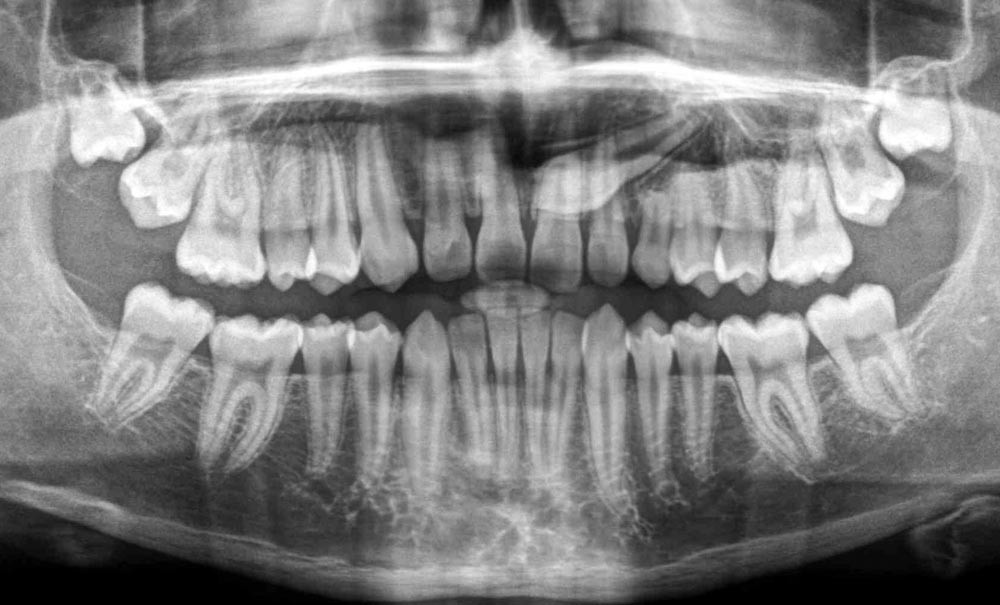

1. QUIZ 1 : Que voyez-vous sur cette radiographie panoramique ? La dent 23 est-elle située du côté vestibulaire ou du côté palatin ?

Que voyez-vous sur cette radiographie panoramique ? La dent 23 est-elle située du côté vestibulaire ou du côté palatin ?

À la lecture de cette radiographie panoramique (fig. 1), on note la persistance de la 63 associée à l’inclusion de la 23 dont l’axe d’éruption est dirigé en mésial en regard de 21 et 22. Concernant la position vestibulaire ou palatine de la 23, en l’absence de clichés rétro-alvéolaires en incidence décalée, il est difficile de déterminer avec précision son emplacement. Cependant, la visibilité marquée des racines des 11 et 12 suggère une probable position palatine de la 23. On note également un retard d’éruption pour les secondes molaires maxillaires. De plus, on observe l’absence des germes de 38 et 48 (agénésies). Enfin, les condyles droit et gauche semblent asymétriques, ce qui est sans doute dû au positionnement droite-gauche du patient pendant la prise du cliché radiographique.